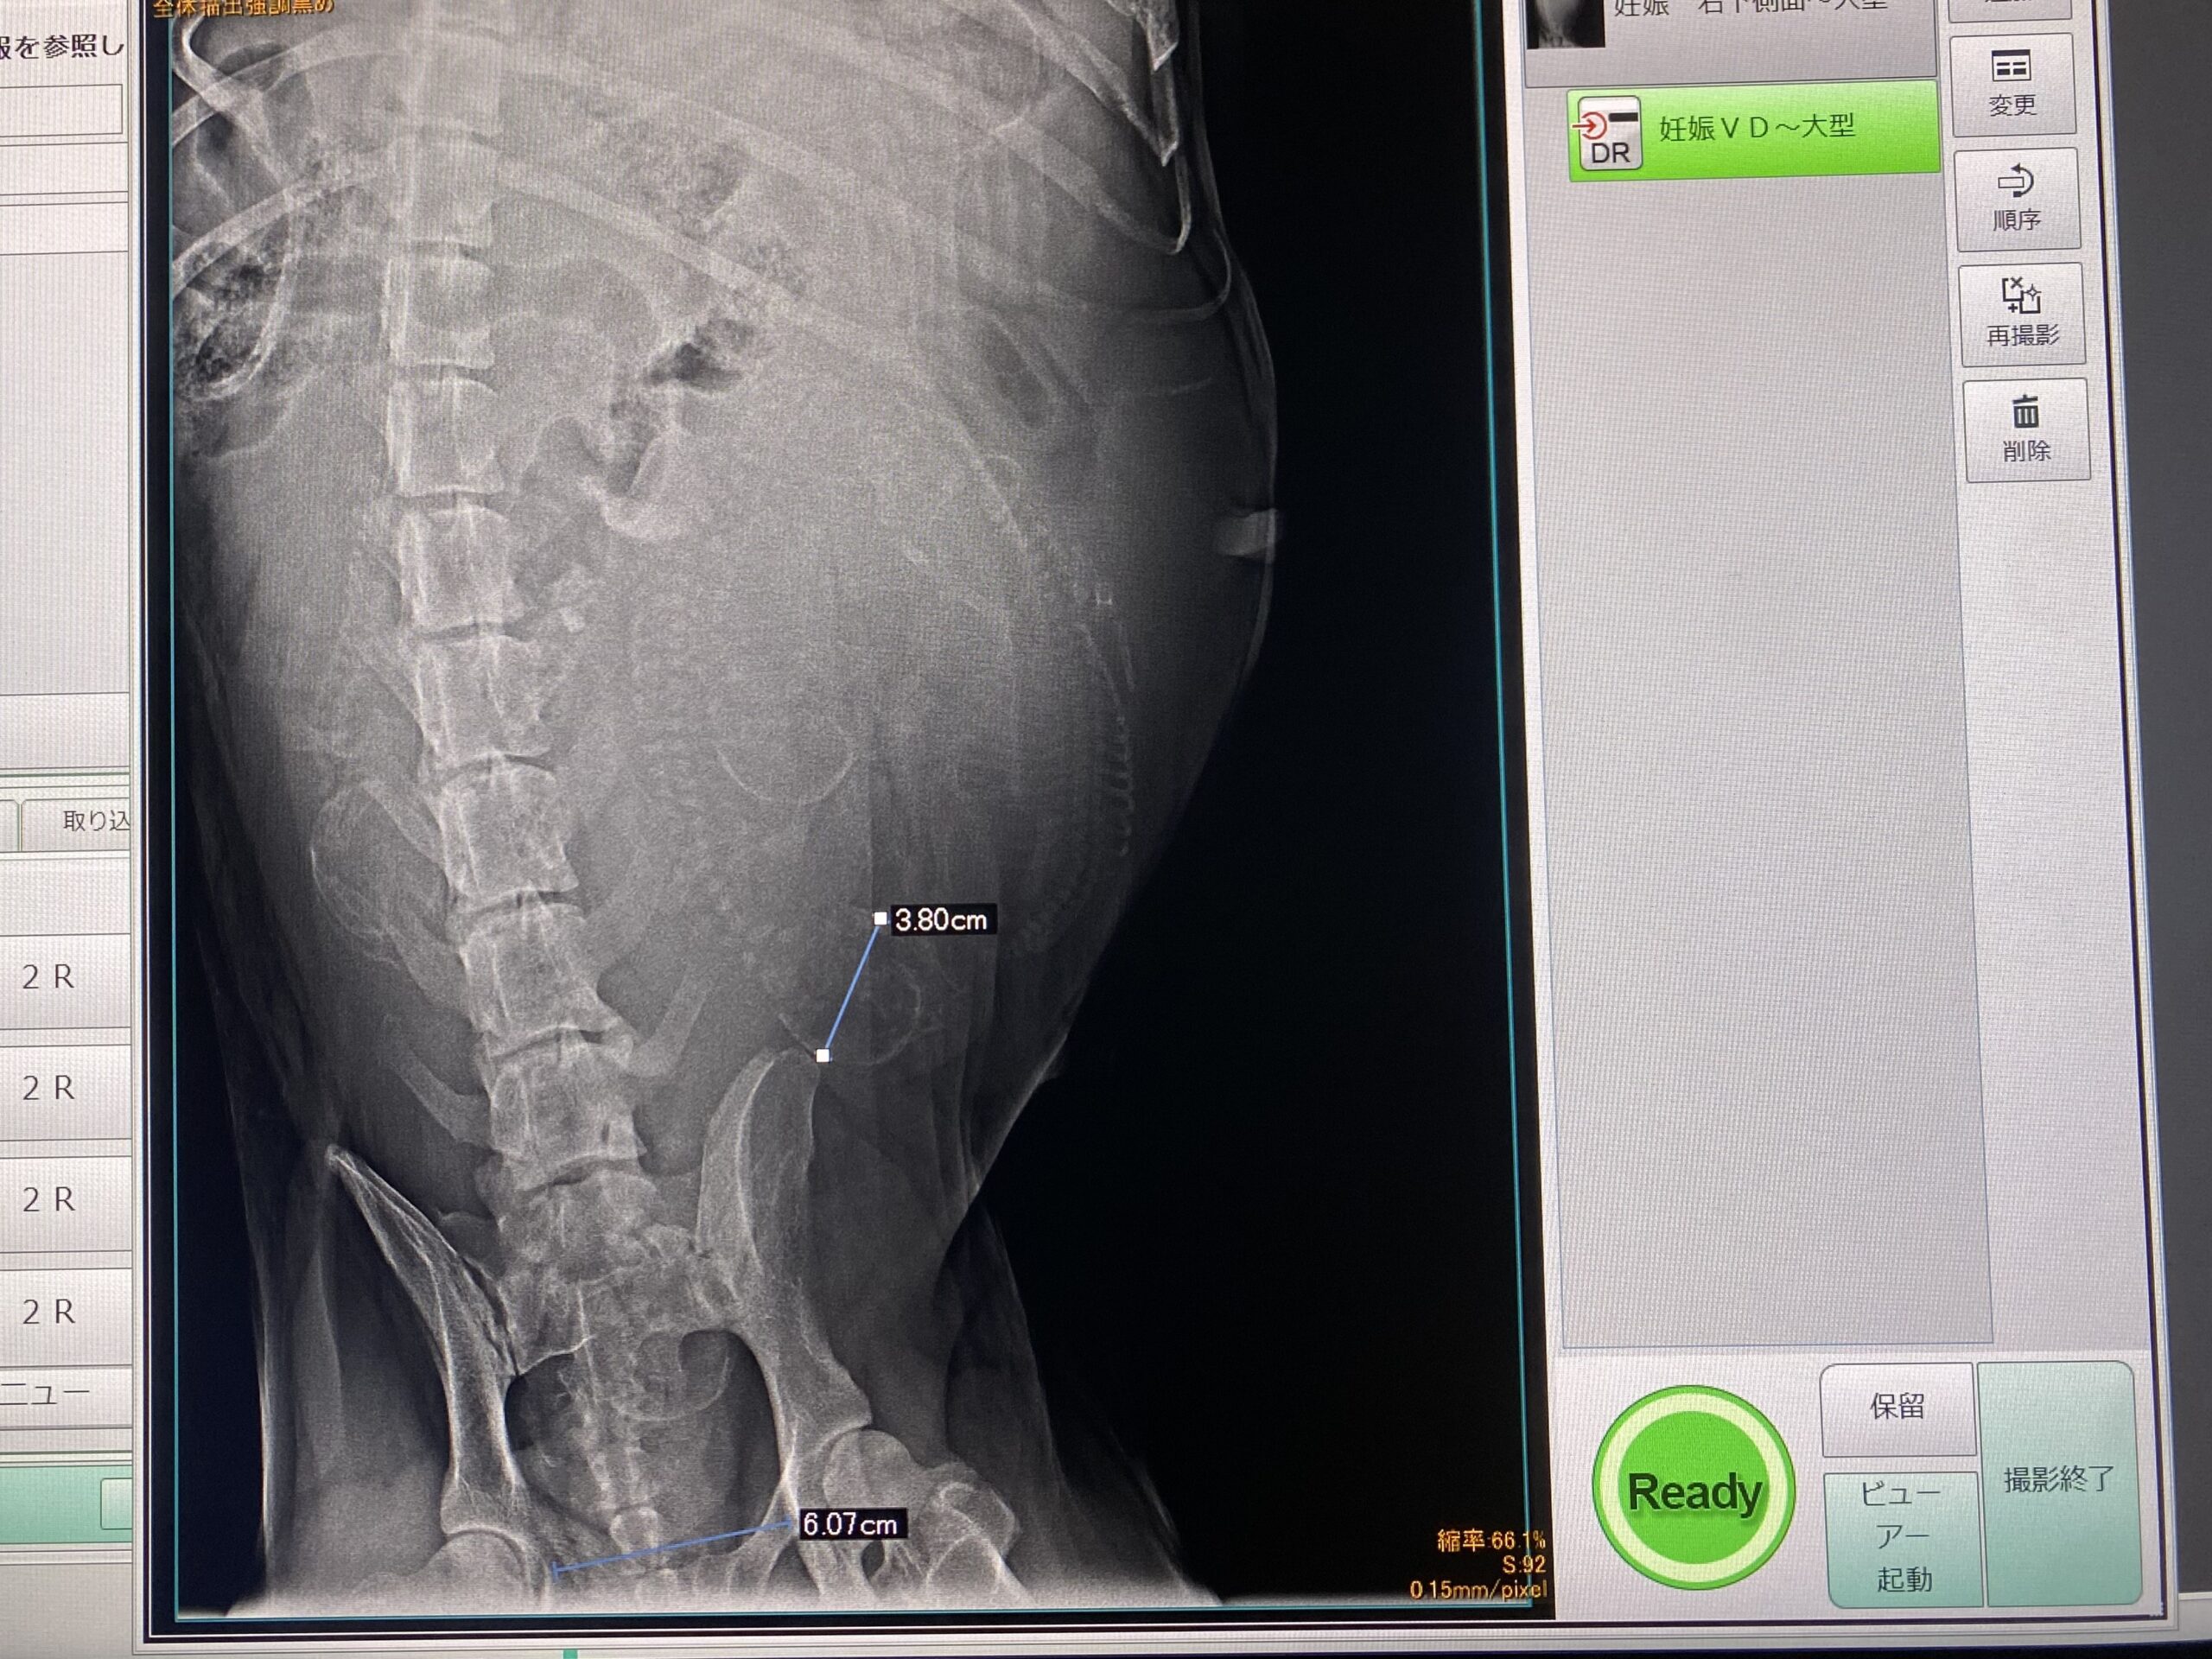

エコーで胎児が元気に育っている事を確認して、レントゲンで大まかの頭数と産道を通過できるサイズかを確認。

頭数は5-6頭かなぁ〜

仔犬のサイズは産道は通過できるなので自然分娩との事になりました。